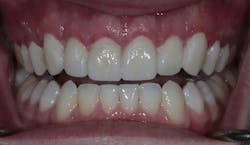

After experiencing the comparative advantage the provisional teeth offered him, the patient was ready for the final restorations to be placed. After placement, the patient left the office with both an esthetic and functional upgrade to take on life after college with confidence, featuring 10 porcelain veneers across his maxillary teeth.

As a review, the digital approach greatly enhanced an outcome built upon accurate and predictable surgery, conservative tooth preparation, and tailored esthetics that both enhanced the patient’s natural features and addressed his main concern in an efficient and well-communicated series of steps.